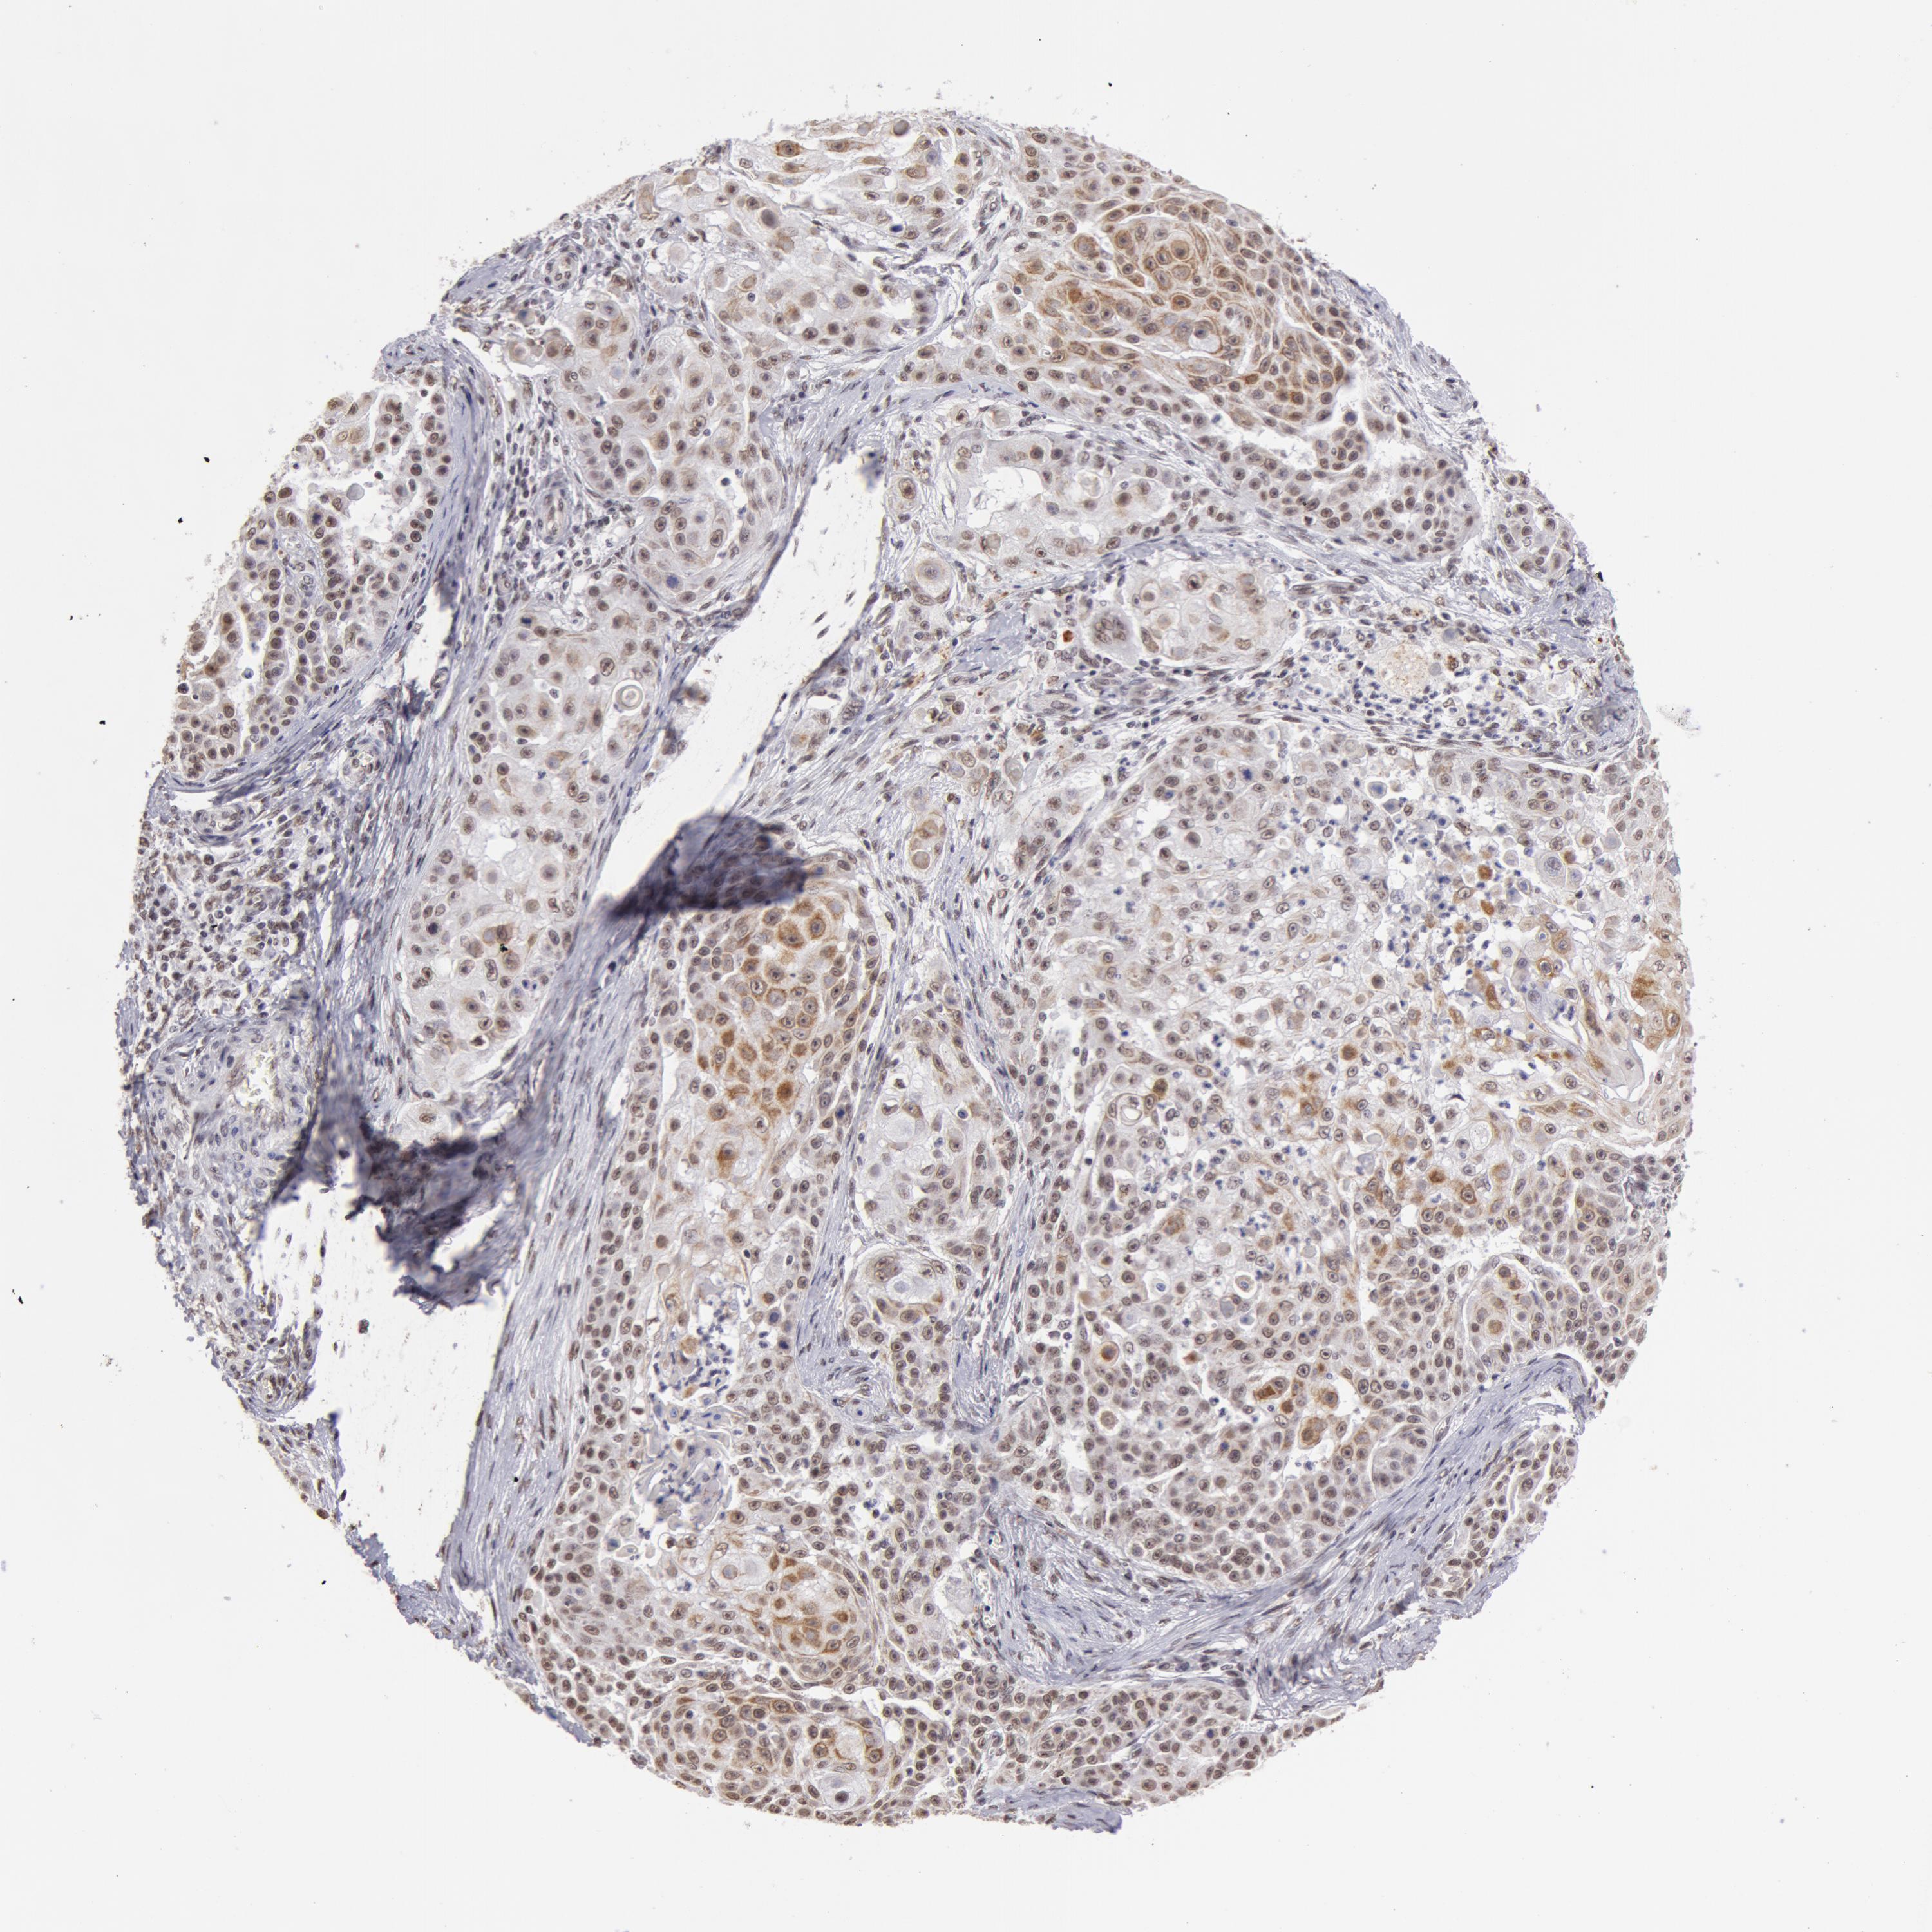

SKIN CANCER - Protein expressioni

A mouse-over function shows sample information and annotation data. Click on an image to view it in a full screen mode. Samples can be filtered based on level of antibody staining by selecting one or several of the following categories: high, medium, low and not detected. The assay and annotation is described here.

Antibody stainingi

Antibody staining in the annotated cell types in the current human tissue is reported as not detected, low, medium, or high, based on conventional immunohistochemistry profiling in selected tissues. This score is based on the combination of the staining intensity and fraction of stained cells.

Each image is clickable and will lead to virtual microscopy that enables deeper exploration of all samples and also displays staining intensity scores, fraction scores and subcellular localization as well as patient and tissue information for each sample.

Antibody HPA001460

Staining

High

Medium

Low

Not detected

Intensity

Strong

Moderate

Weak

Negative

Quantity

>75%

75%-25%

<25%

None

Location

Nuclear

Cytoplasmic/membranous

Cytoplasmic/membranous,nuclear

Squamous cell carcinoma, NOS

Basal cell carcinoma